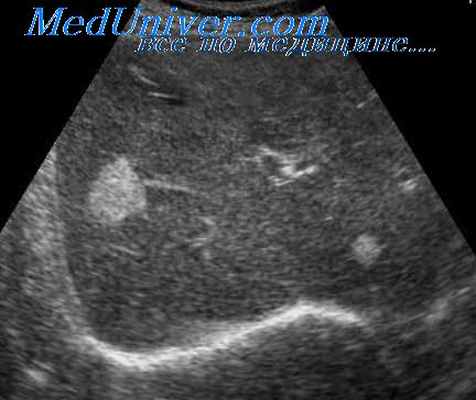

Врожденные простые кисты печени

Врожденные простые кисты печени встречаются редко. Постулируется, что эти кисты возникают в результате аберрантного развития желчевыводящих путей внутриутробно с обструкцией, приводящей к скоплению жидкости, расширению протоков и потере связи с нормальными желчевыводящими путями. Они также могут возникать после закупорки перибилиарных желез вследствие врожденного порока развития или другого болезненного процесса.

Врожденные билиарные кисты (врожденные кисты, поликистоз печени) могут быть солитарными или множественными, причем последний тип может быть проявлением поликистоза, сочетающегося с поликистозом почек и других органов. Кисты обычно мелкие, но могут иметь крупные размеры, приводят к гепатомегалии. Просветы кист заполнены прозрачной жидкостью. При микроскопическом исследовании видны кисты, выстланные кубическим эпителием; можно обнаружить наличие внутри- и внеклеточной слизи.

В соединительной ткани вокруг кист иногда отмечают лимфоидную инфильтрацию. Описаны редкие наблюдения возникновения рака желчных протоков на фоне врожденных билиарных кист.

Киста печени

Чаще встречаются непаразитарные кисты. Учитывается возможность поликистозной болезни, а также солитарных и множественных истинных и ложных кист печени.

Большинство кист небольшие (диаметром 1-5 см), чаще встречаются у женщин. Значительная часть их имеет бессимптомное течение. У ряда больных отмечаются боли в правом подреберье, у одних — постоянные, у других — периодические. Существенную помощь оказывает использование УЗИ и КТ (или ЯМР), обладающие высокой разрешающей способностью. Необходимо учитывать возможность поликистоза печени.

Дифференциальная диагностика простых кист проводится также с паразитарными кистами печени (эхинококкоз). В пользу последних говорят положительные реакции с эхинококковым антигеном и Кацони, а также обнаружение в зоне опухолевидного образования обызвествлений, хотя и гемангиомы изредка могут обызвествляться.

Лечение кисты печени

Часть непарзитарных кист печени также подлежит оперативному лечению в связи с реальной возможностью их разрыва, инфицирования и кровоизлияния в просвет кисты. Кроме того, быстро растущие крупные кисты приводят к нарушению функций печени вследствие атрофии и замещения печеночной паренхимы кистозным образованием. Среди операций наиболее часто используют резекцию печени, перицистэктомию и вылущивание кисты.

В последние годы широкое распространение получили транспариетальные пункции кист под контролем УЗИ или КТ. После аспирации содержимого в просвет кисты вводят 96*раствор этилового спирта для склерозирования внутренней оболочки кисты. Эта операция эффектина приразмере кисты до 5 см. Если нет эффекта от данных способов лечения или киста имеет больший размер, показана операция — лапароскопическое иссечение участка кисты с последующей деэпителизацией внутренней оболочки кисты аргонусиленной плазмой или расфокусированным лучом лазера. Аналогичная тактика используется и при поликистозе печени. При осложненном поликистозе печени (нагноение, кровотечение, озлокачествление, сдавление крупными кистами желчных путей, воротной или полой вены) показано оперативное лечение. Обычно выполняют фенестрацию (вскрытие выступающих над поверхностью печени кист) с последующей деэпителизацией внутренней оболочки кисты.